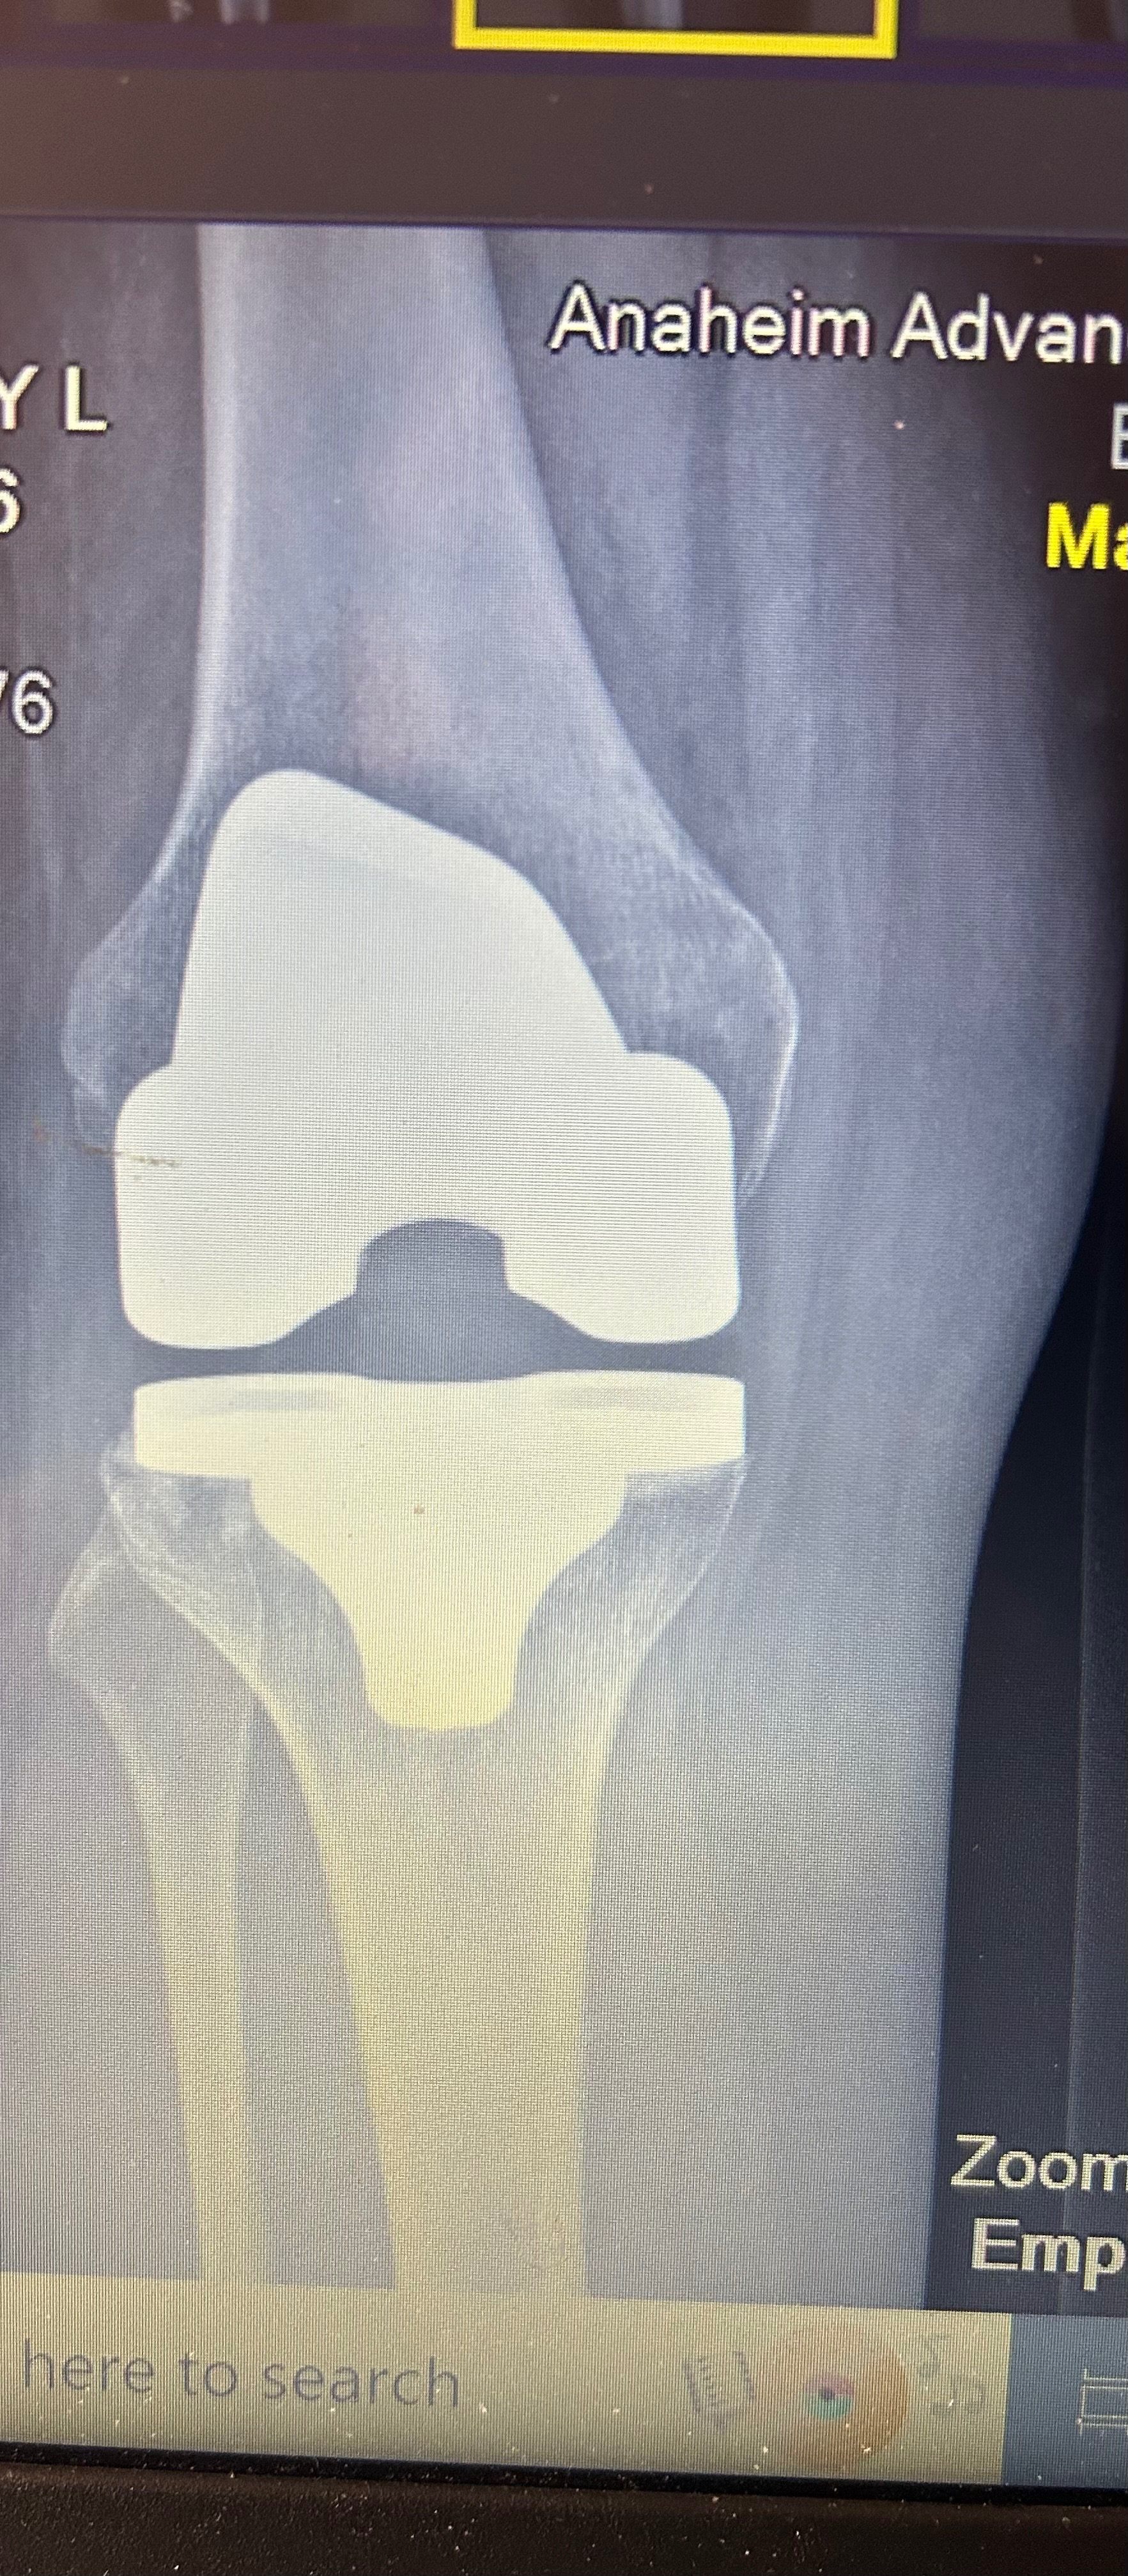

In September 2024, I was involved in a severe car accident that left me with significant injuries, including the need for a full knee replacement surgery. Since the accident, I have been unable to work and have an overwhelming amount of medical expenses. The person who hit me has a minimum policy and I have been funding everything myself and I am tapped out.